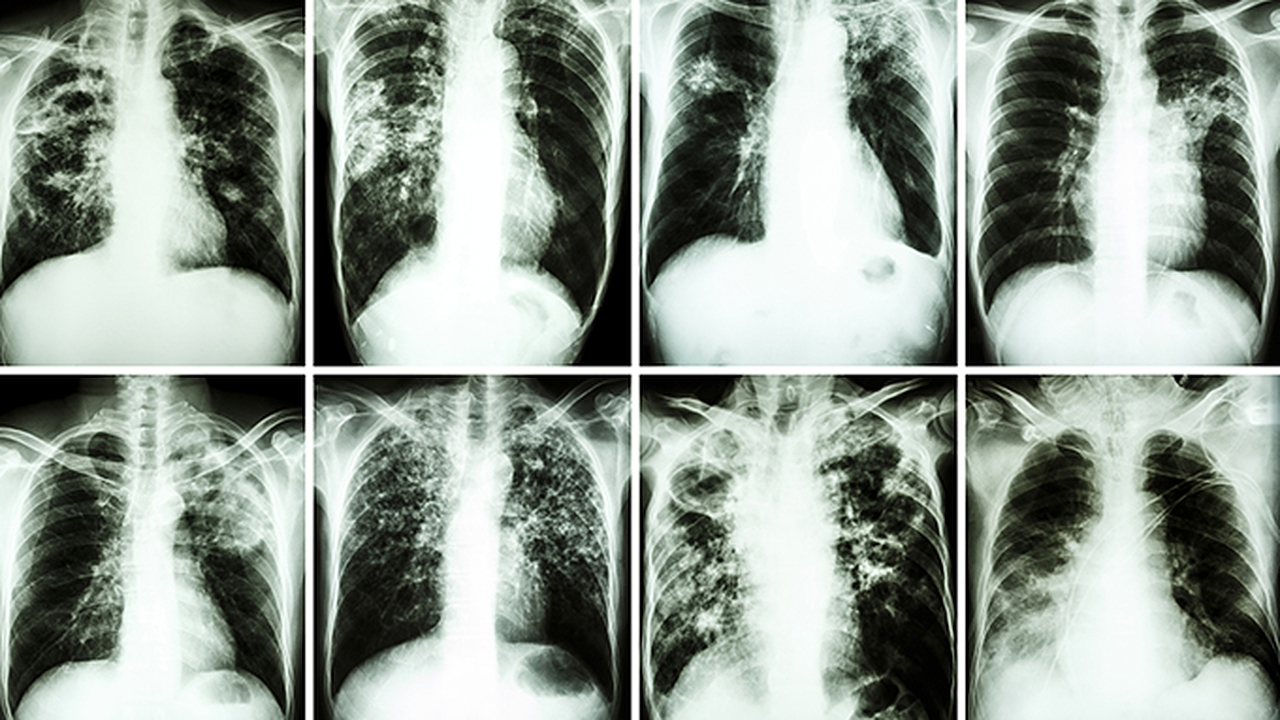

山东省立医院是济南市乃至山东省内癌症筛查技术的医疗机构之一。医院拥有国际的筛查设备,包括低剂量螺旋CT、乳腺钼靶、胃肠镜等。医院开展的癌症筛查项目覆盖肺癌、乳腺癌、胃癌、结直肠癌等多种高发癌症。筛查流程科学规范,从预约到检查再到报告解读形成完整闭环。医院还针对不同人群制定个性化筛查方案,如针对长期吸烟者的肺癌筛查套餐、针对家族遗传史人群的专项筛查等。医院每年筛查出大量早期癌症病例,为患者争取了佳治疗时机。

山东大学齐鲁医院在癌症早筛早诊方面具有显著优势。医院肿瘤防治中心配备PET-CT、核磁共振等高端影像设备,能够发现微小病灶。医院开展的肿瘤标志物检测项目齐全,结合影像学检查可大大提高癌症检出率。医院特别重视消化道肿瘤筛查,无痛胃肠镜检查技术成熟,患者接受度高。针对女性高发的乳腺癌和宫颈癌,医院提供专业筛查服务,采用超声、钼靶和HPV检测相结合的方式。医院还建立了完善的筛查随访制度,对高风险人群进行长期跟踪。

济南市中心医院的癌症筛查工作以规范化和化为特色。医院体检中心设有专门的肿瘤筛查套餐,可根据年龄、性别、职业等因素进行个性化选择。医院引进的AI辅助诊断系统可提高影像筛查的准确性,减少漏诊误诊。针对常见的肺癌筛查,医院采用低剂量CT技术,辐射量小且图像清晰。消化道肿瘤筛查方面,医院开展无痛胃肠镜检查,配备高清内镜系统。医院还提供肿瘤标志物联合检测,通过多项指标综合分析提高筛查效能。筛查后可疑病例可快速转入专科进一步诊治。